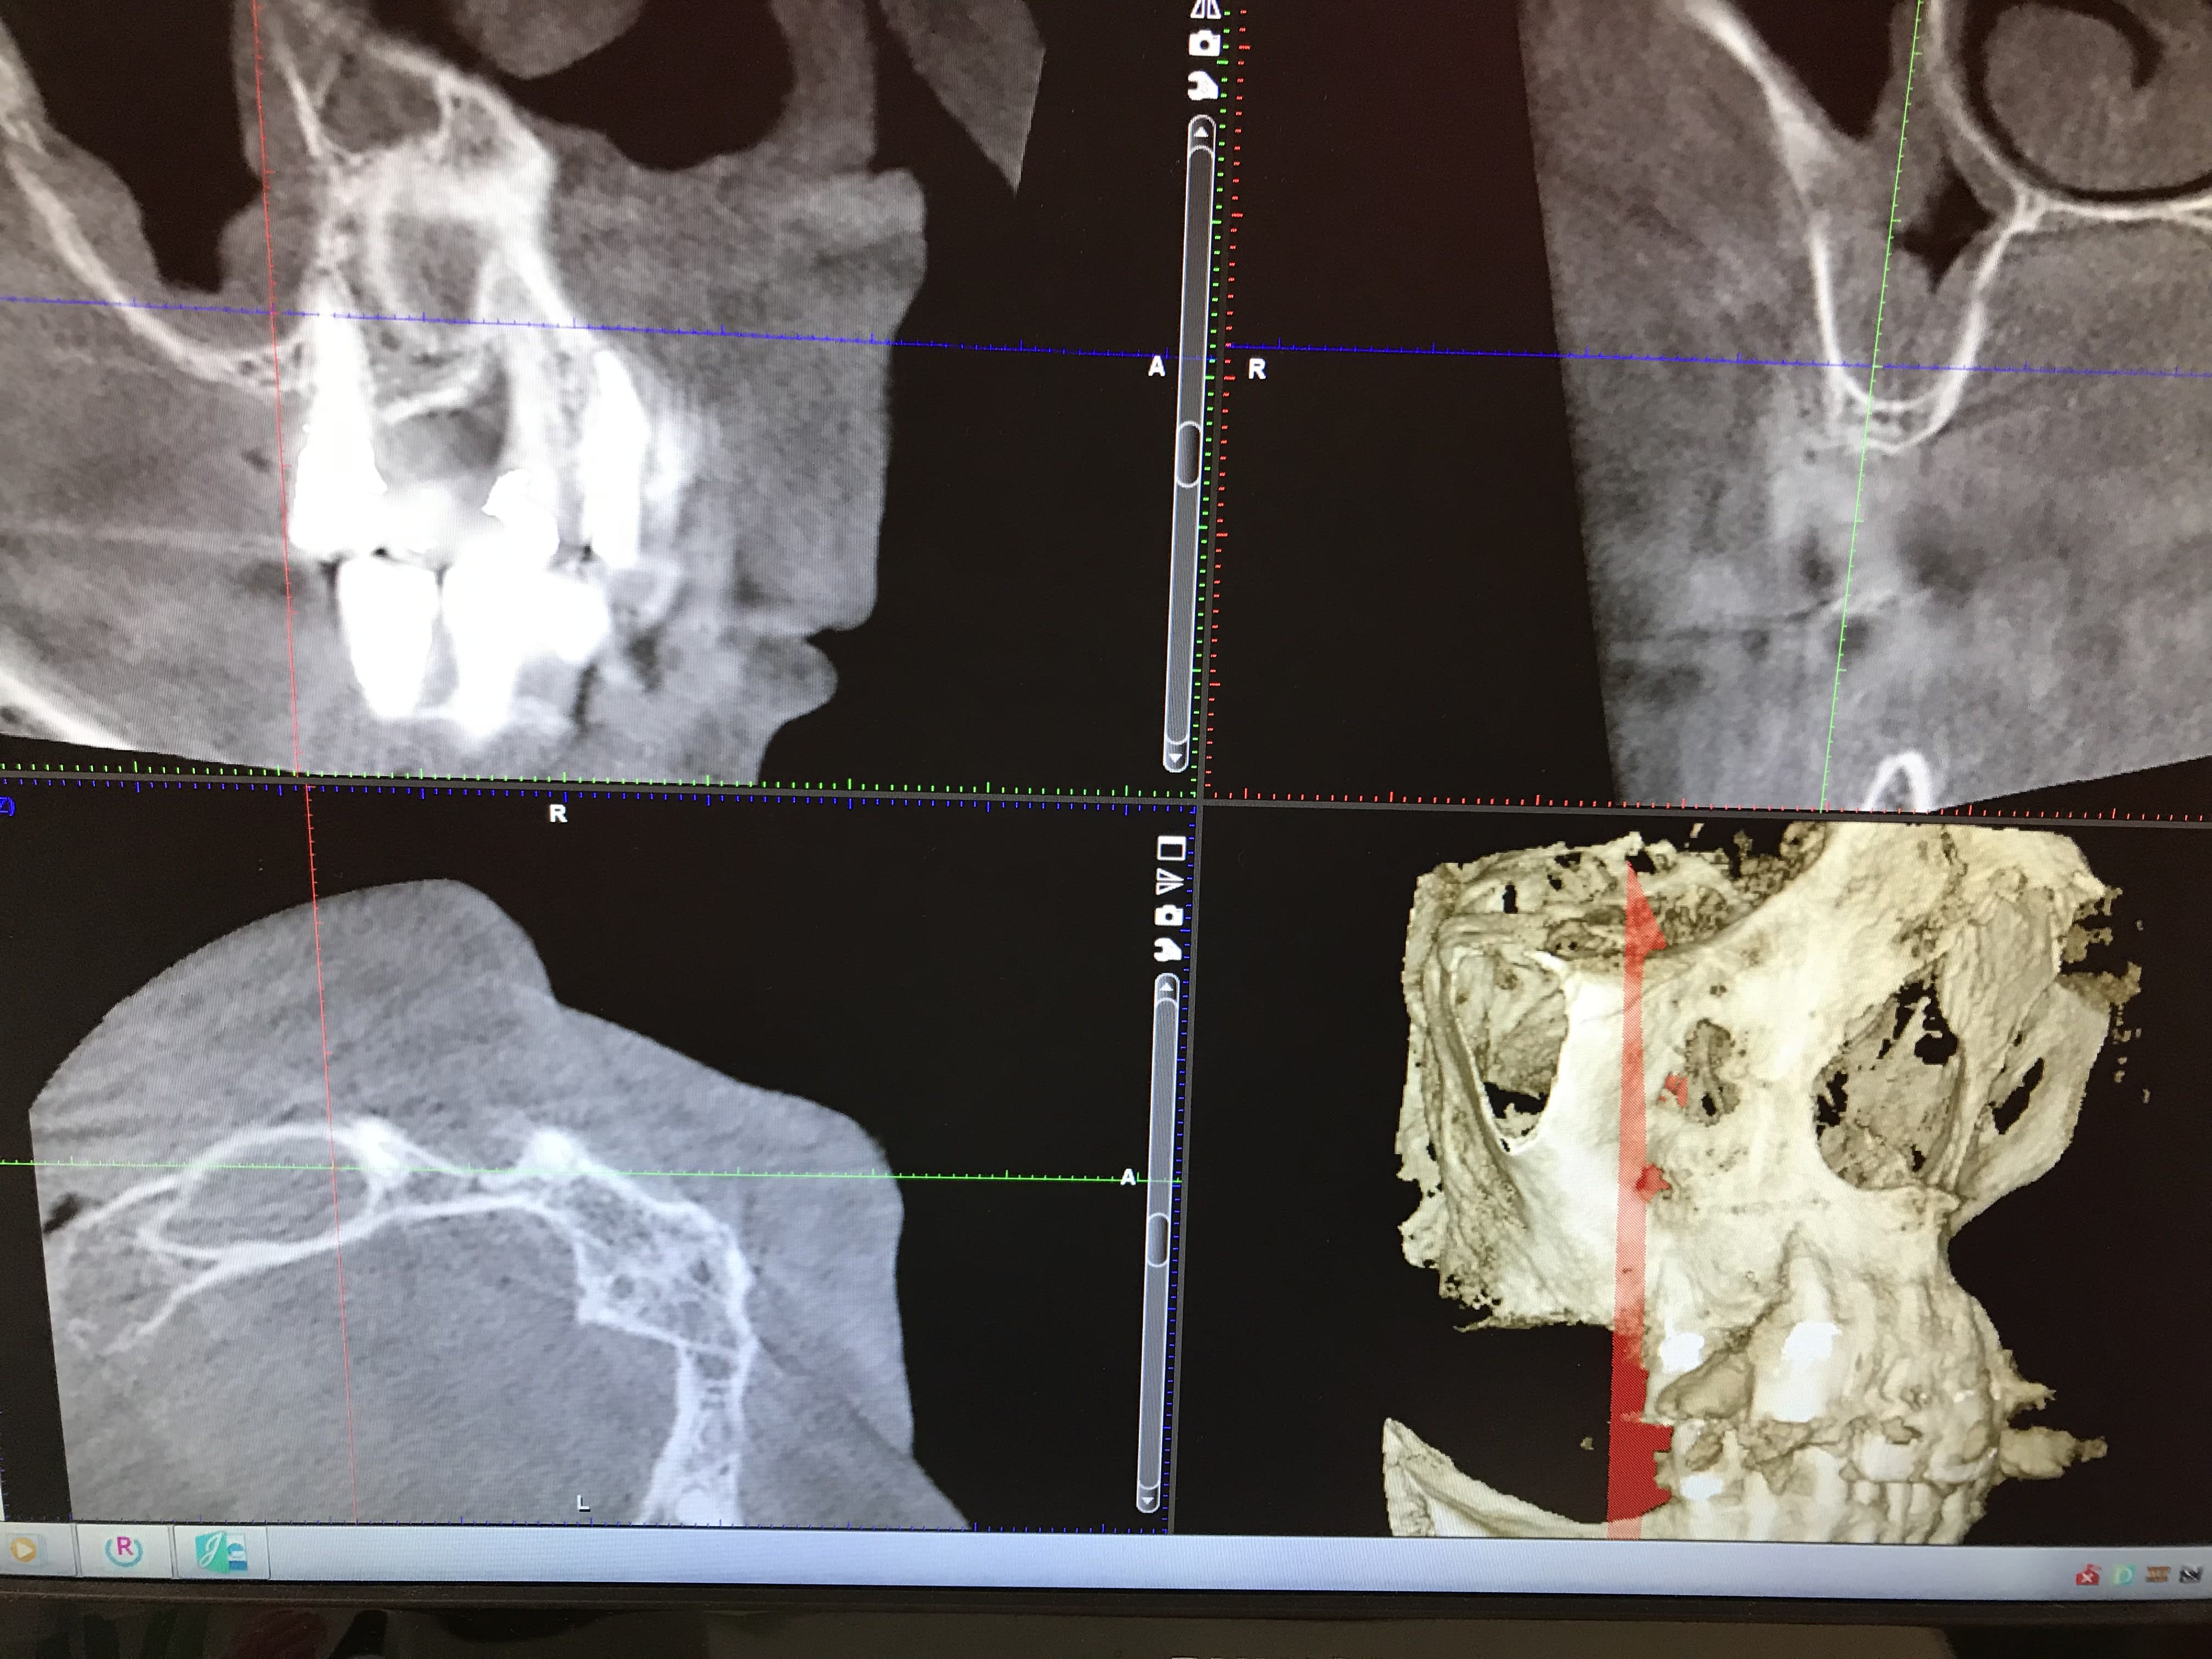

Patiente avec pilier de bridge 13 fracturé + 15 paro mobile + 25 paro mobile + 22 légèrement mobile. Les seules dents "viables" sur l'arcade sont 11, 21 et 22 et la 12 a été extraite entre temps.

Sur les coupes conebeam, très peu d'os au niveau de 13 et surtout 14 en épaisseur, un peu plus au niveau de 23 et 24 et pas assez d'os au niveau de 15 et 25 (présence des sinus).